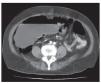

Se decide su ingreso hospitalario a cargo del departamento de Cirugía General para manejo protocolizado. Durante su estancia hospitalaria, persiste con dolor abdominal generalizado, tipo cólico, de intensidad moderada, constante, sin irradiaciones ni exacerbaciones, náusea ocasional, sin vómito; refiere distensión abdominal importante e incapacidad para canalizar gases de manera progresiva. Se solicita tomografía computarizada, la cual muestra distensión de ciego > 12 cm y distensión de colon ascendente, con neumatosis intestinal y niveles hidroaéreos (figuras 3-5).

Figura 3 TAC de abdomen con distensión cecal.

Figura 4 Neumatosis intestinal en TAC de abdomen.

Figura 5 TAC de abdomen con dilatación cecal y neumatosis intestinal.